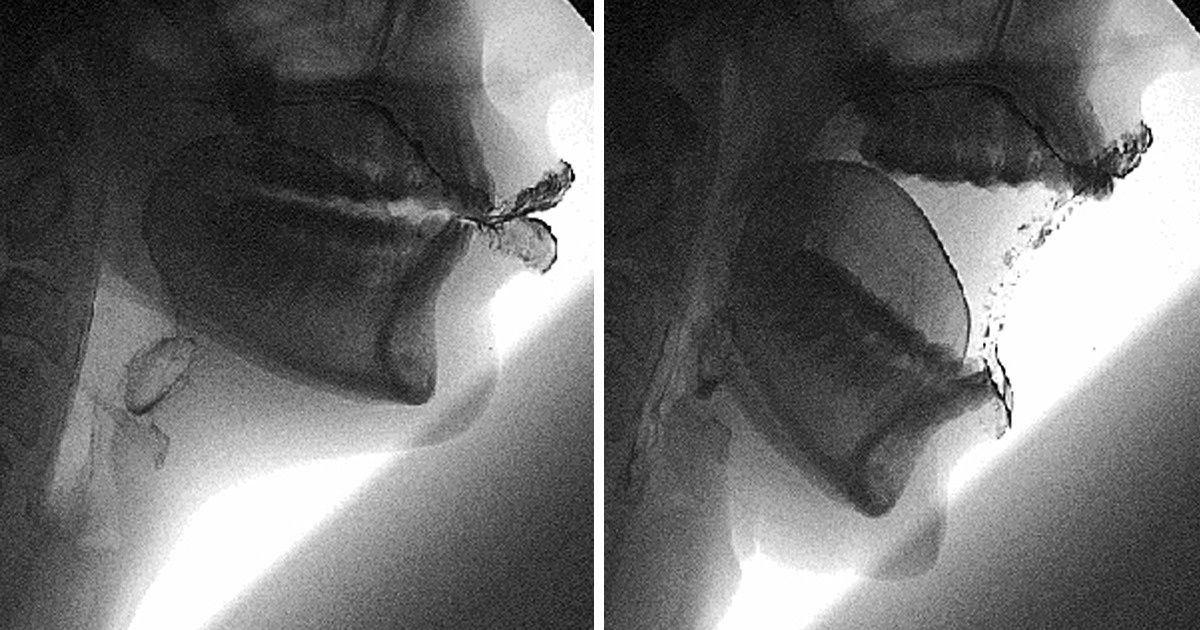

Como dizem os cientistas, no útero da mãe uma pessoa passa por todos os estágios do desenvolvimento evolucionário. Portanto, em algum momento tivemos cauda, brânquias e membranas entre os dedos. Talvez você já soubesse disso, mas nunca viu.